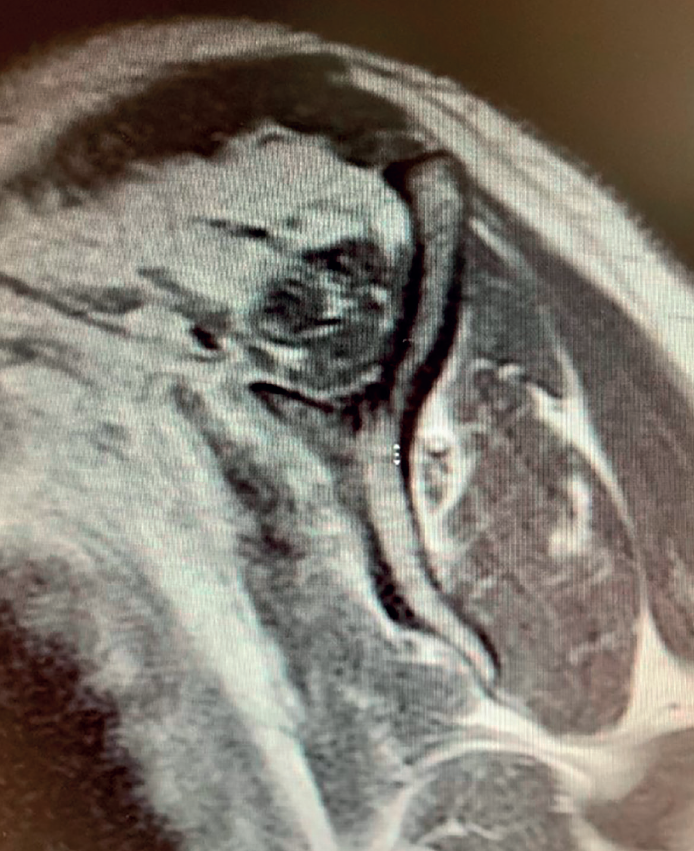

Boileau in 2005 or Simovitch in 2007(28,32) concluded that reverse replacement is unable to secure the restoration of external rotation. In many patients, only the teres minor will be able to afford active external rotation. If the teres minor presents rupture, retraction or adipose degeneration (which can be assessed by magnetic resonance imaging or computed tomography), we can predict a poorer outcome in these individuals, with an external rotation deficit(33,34). The lack of external rotation may prove quite disabling, especially in patients that use the arm in abduction. For this reason, some investigators such as Longo, in 2011(35), indicate the possibility of latissimus dorsi transfer to the reverse replacement implant, to restore external rotation in the patient.